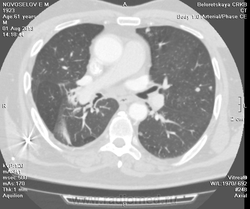

Мужчина оперирован по поводу BL щитовидной железы.Неоднократно проходил КТ в других лечебных учреждениях, у нас- впервые.Ставились заключения:MTS в лёгкие и лимф.узлы средостения слева.Образование слева увеличилось.Жалуется на одышку, не верит в заключение о MTS,просит узнать мнение других специалистов.

Метастазов в легкие не вижу. Похоже на лимфоузел в головке левого корня. Если позволите, запаздываете с началом исследования, плотность контраста в легочных артериях должна быть выше, чем а аорте. А одышка, не мудрено, легочная ткань диффузно уплотнена по типу "матового стекла", написал бы какую-нибудь интестициальную пневмонию, по типу альвеолита, может быть и гиперчуствительный пневмонит (не разберу есть или нет внутридольковые очажки), посмотреть бы изначально легочное окно, а не восстановленное из мягкотканного.

В диф. ряд: саркоидоз, атипичная форма.

Кажется,я понял,что Вы имели ввиду.Очажки стрелочкой указал.Согласен с тем,что очаги на фоне отображеничя сосудов кажутся фантазией,но они присутствуют.

Коллега, вынужден извинться и дезавуировать свой первый пост. Пересмотрел. Да, есть очаги, и они - вероятнее всего, метастазы.

Единственное,что напрягает,так это то,что эти изменения у пациента более 1,5 лет.А вид внешний у него не так уж и плох.А слева это всё-таки лимфоузел, а не периферическое образование в S3?

Думаю, да. Слишком близко лежит к легочной артерии.